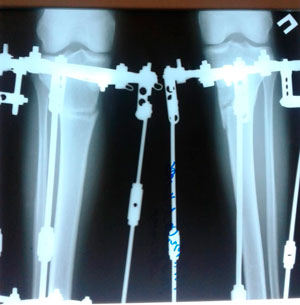

Диагноз: Варусная деформация голеней. Явление деформирующего Артроза II степени. Боль в коленных суставах.

Дата операции - 09.10.2019г.

на фиксации